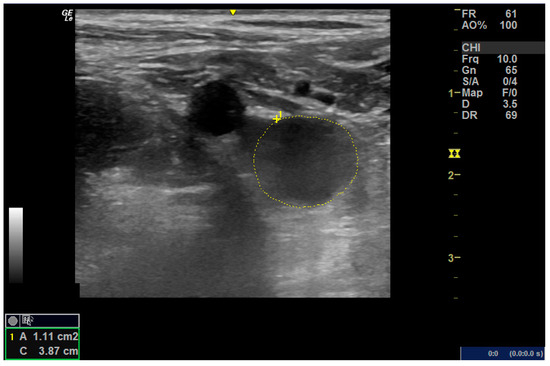

Color Doppler techniques were conducted using the vascular setting of the same ultrasound machine (Next Generation LOGIQ e ultrasound; General Electric, Fairfield, CT, USA). Participants were positioned supine while obtaining short- and long-axis images of the femoral artery in the anterior groin region. For the popliteal artery, participants assumed a prone position with their knees comfortably extended, and the transducer was placed in the popliteal fossa to capture the necessary images. Grayscale pulsed and color Doppler flow imaging were employed during both systolic and diastolic intervals. Cross-sectional areas of the femoral and popliteal arteries were calculated using lumen measurements from transverse images, as per the GE measurement settings (Figure 1A,B). The resistance index, systolic/diastolic ratios, and pulsatility index were computed to evaluate blood flow from the generated waveform [14] (Figure 2).

Figure 2. Cross-sectional area of the femoral artery.